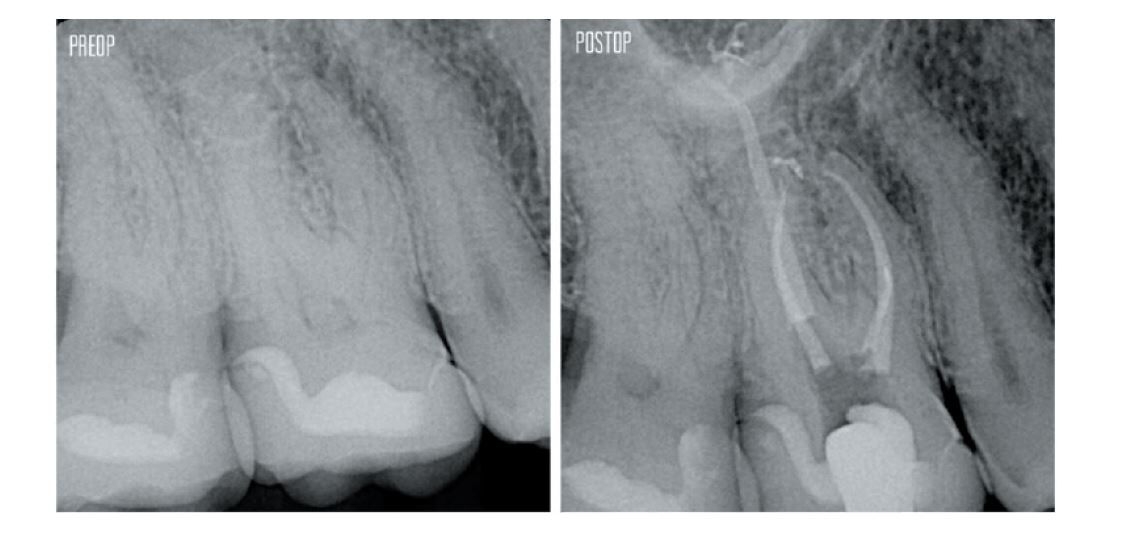

Retaining dentin serves as the critical base for a quality restoration following root canal treatment. The more dentin preserved during an endodontic treatment, the more options there will be to perform a successful, durable restoration.1

TruNatomy preserves as much dentin as possible1 and offers a complete solution including matching irrigation and obturation.